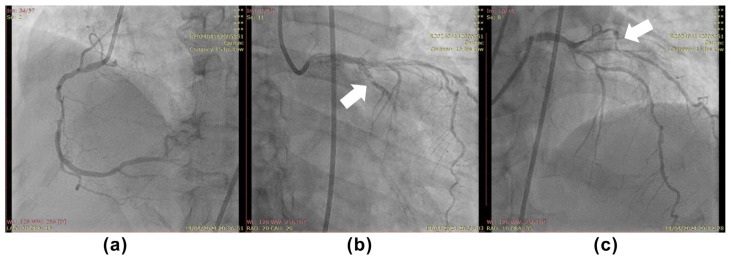

Identifying the infarct-related artery (IRA) in a non-ST-segment-elevation acute myocardial infarction (NSTEMI) can be very challenging, particularly in a hospital that cannot perform intracoronary imaging due to certain limitations. This is because, by angiography, most patients present with multivessel coronary artery disease (CAD), diffuse disease, or non-significant CAD. We present a case of a 60-year-old female patient presented with substernal chest pain and palpitations of 6 h duration. The first hospital contact 12-lead electrocardiogram (ECG) showed ventricular tachycardia (VT) with unstable hemodynamics, after stabilization patient was transported to the catheterization laboratory for immediate percutaneous coronary intervention (PCI). With a clue of VT morphology, post-converted ECG, and coronary angiography, the patient successfully underwent PCI in the left circumflex artery.